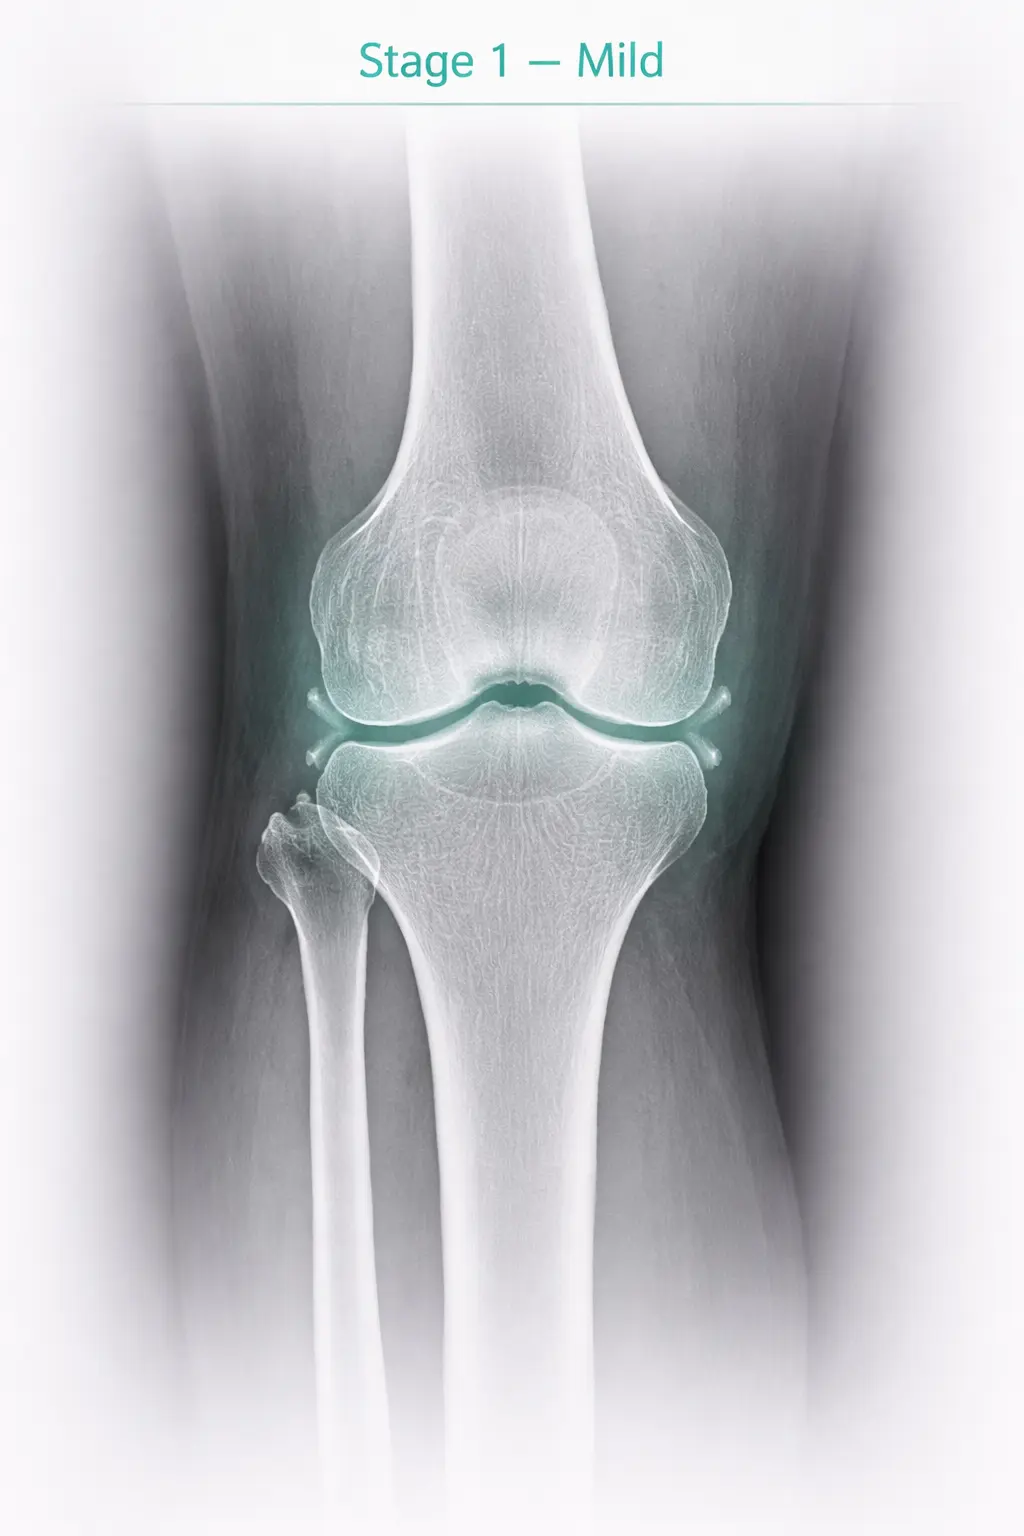

1

Stage 1

Mild

Symptoms

• Pain just started

X-ray Findings

X-ray almost absolutely normal

Stage 1 - Mild osteoarthritis in knee joint X-ray